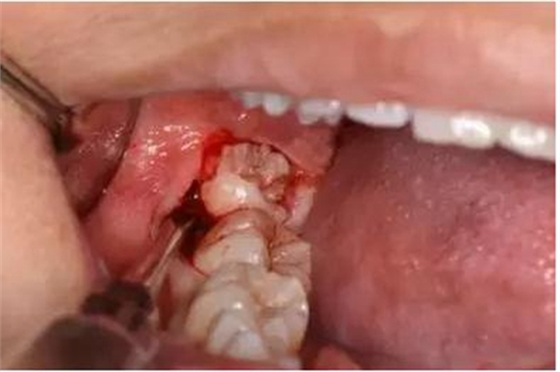

圖9.翻小瓣、用骨膜剝離器輕柔牽拉頰側(cè)齦瓣、暴露48合面

圖10.普通牙挺放置在48牙冠的近中根面與牙槽嵴頂之間,采用推力和挺力,挺松48.

圖11.以頰側(cè)骨板做支點(diǎn)、往上脫位

圖12. 近中、頰側(cè)兩個(gè)部位用挺使48牙冠完全脫位